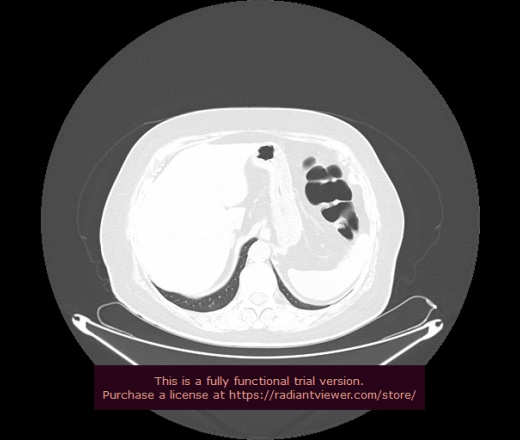

Уважаемые коллеги, если имеется интерес, сможете ли Вы спрогнозировать дальнейшее +-одинаковое течение процесса у 4 данных разных пациентов? Зацепиться где-то можно очень просто, где-то нельзя.